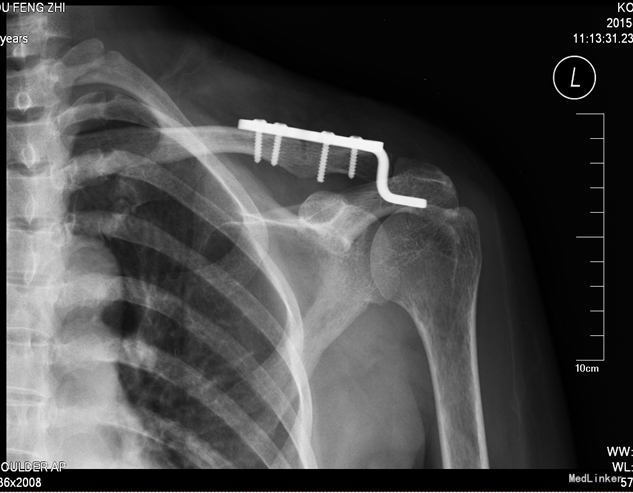

中医诊断:左肩锁关节脱位(气滞血瘀)西医诊断:左肩锁关节脱位 诊断:切开复位钩钢板内固定术 中医辨证论治:根据骨伤科三期辨证理论,早期因瘀血停滞影响骨痂生长,故以活血化瘀,消肿止痛为 主,应用桃红四物汤;中后期补益肝肾,补气养血,应用愈骨胶囊等药物应用。现患者属于骨折早期, 可运用桃红四物汤加减对症治疗,方药如下: 桃仁10g 红花10g 当归12g 川芎12g 赤芍12g 穿山甲6g 柴胡12g 黄芩10g 香附12g 延胡索15g 续断15g 生地12g 甘草6g 3剂 用法:每日一剂,水煎服400ml,分早晚两次温服。 中医调护:避风寒,慎起居,忌生冷,畅情志。

术后复查X线片示骨折复位良好,内固定在位且牢靠。根据骨伤科三期辨证理论,早期因瘀血停滞影响骨 痂生长,故以活血化瘀,消肿止痛为主,应用桃红四物汤。术后证属肝肾亏虚,气血不足,治以补益肝 肾,补气养血,应用愈骨胶囊等药物促进骨折愈合。术后嘱患者继续石膏托外固定,注意陪护,3月内扶 双拐、按指导患肢不负重功能锻炼;休息3个月,加强营养,促进骨折愈合;继续中药应用,促进骨折愈 合;定期复查,(1月、3月、6月);不适随诊。 本病例中医药应用结合手术复位,早期将骨折复位, 中医药早期应用活血化瘀、消肿止痛,可迅速缓解患者症状。中医药中后期应用可促进骨折愈合,加快 术后恢复,可使患者获得满意的术后疗效。